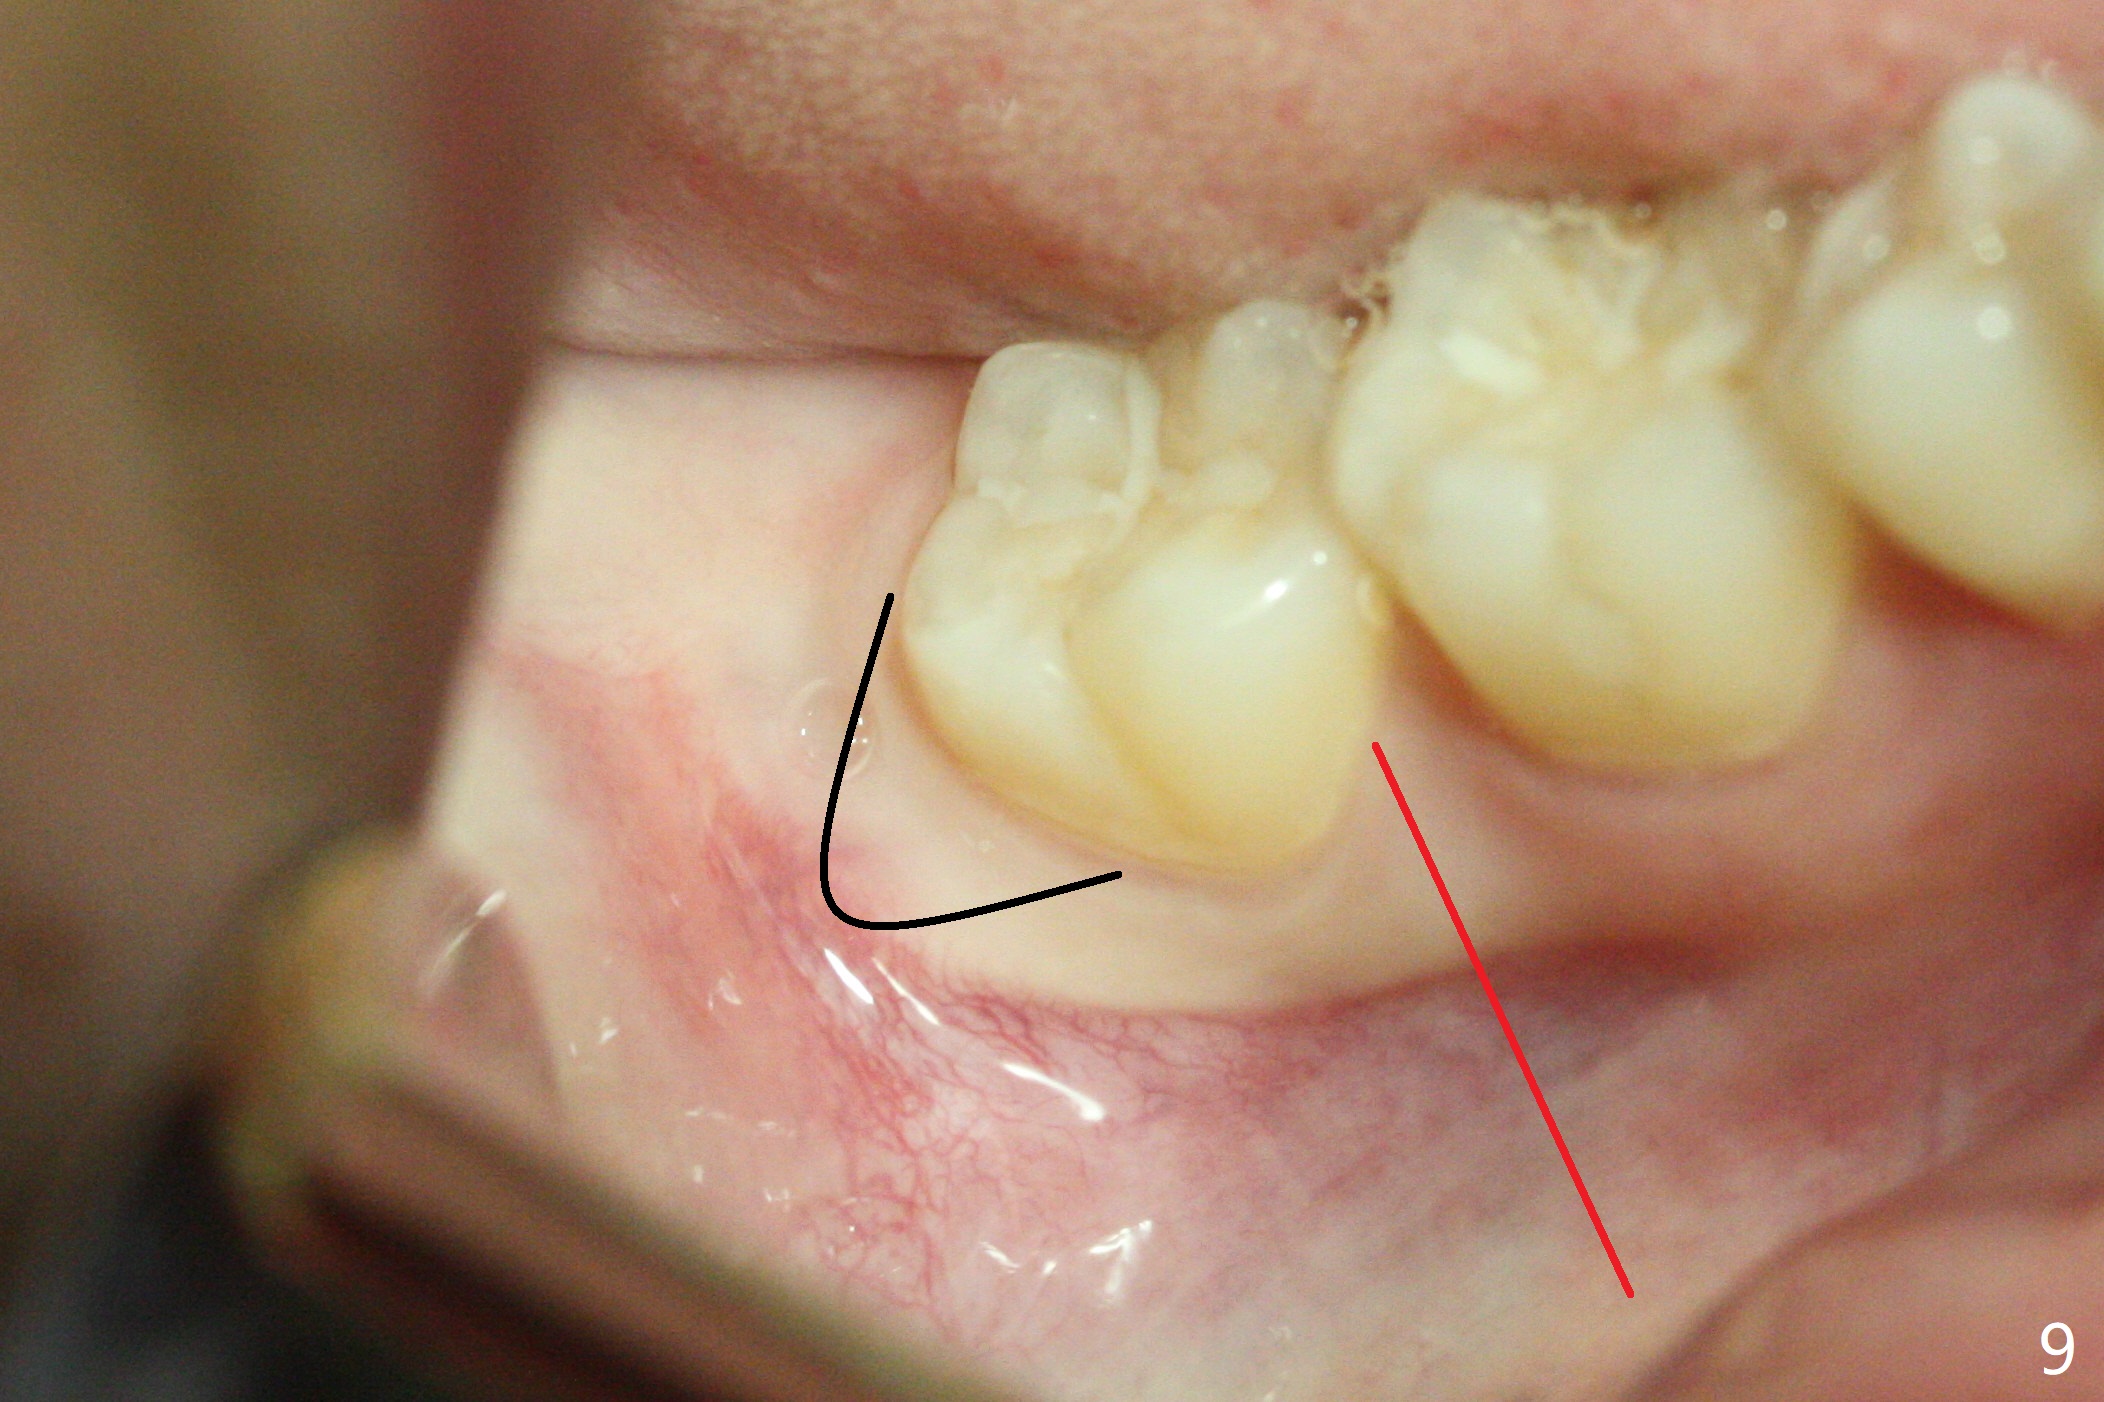

A 25-year-old woman, under our care for the last 11 years (Fig.1-6), returns for #1 and 32 extraction (1 year after #16 and 17 extraction (Osteogen plug)). Preop PA shows that a portion of the lower impacted tooth may be located buccal to the tooth #31 (Fig.4 black dashed line). An accessory incision is moved from distobuccal to midbuccal (Fig.7 arrowheads) to reduce postop loss of bone graft (Fig.8 B) from the incision. In fact the incision should be further moved to mesiobuccal (Fig.9 red line) if buccal impaction is suspected (curved black line). The buccal impaction of #32 of her father is more severe.